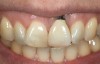

Problem: The implant is placed too facially, and there is significant labial gingival recession, contour change, and mucosal discoloration around the implant, abutment, and crown (Figure 3 and Figure 4). The implant attachment apparatus is intact and healthy, but the patient has a thin periodontal phenotype.

The following case report provides an example of this case scenario: A 28-year-old white female patient presented with her maxillary right lateral incisor significantly longer than the contralateral tooth following restoration of an existing crown that was 10 years old (Figure 3). The patient was dissatisfied with the esthetic appearance of the restoration due to the increased length, recession of the gingival tissues, and discoloration of the surrounding mucosa (Figure 4). Similar to case scenario No. 1, the first step in treatment was to decoronate the healthy implant by placing a flat surgical cover screw and employing a provisional resin-bonded-retained (RBR) prosthesis as a transitional fixed restoration (Figure 5 and Figure 6). The gingival augmentation in situ was allowed to take place for 2 to 3 weeks and was evaluated after that time (Figure 7).

Fig 3. A patient presented with a high smile line and midfacial recession of the maxillary right lateral incisor as evidenced by the increased tooth length compared with the contralateral lateral incisor.

Fig 4. Intraoral view of tooth No. 7 with the gingival zenith more apical than the adjacent central incisor and canine tooth.